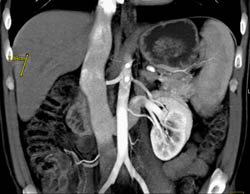

Focal Nodular Hyperplasia (FNH)